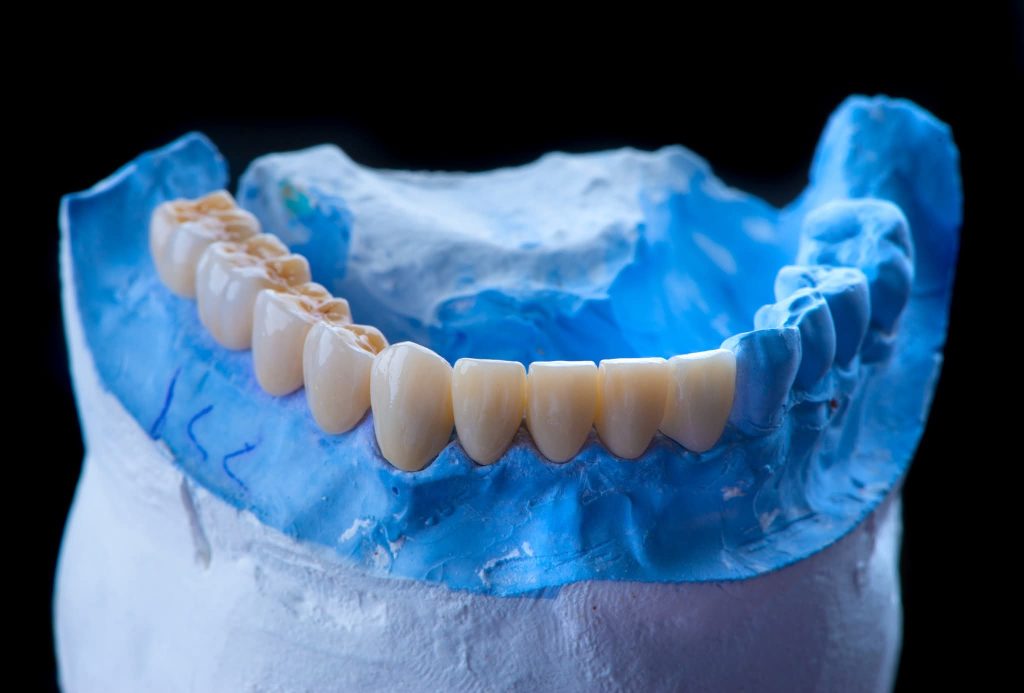

The case was transferred to a semi-adjustable articulator, where the vertical dimension was increased by 5 mm. A diagnostic wax-up and removable prostheses were created at the new vertical dimension, guided by the curve of Spee using Broadrick’s Occlusal Plane Analyzer. Silicone indices were fabricated for both arches.

Preparation of teeth and insertion of the fixed prosthesis.

The lower arch was managed similarly to the upper arch.